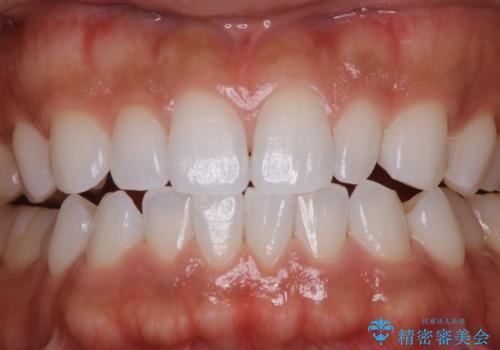

- ¥5500費用は治療当時の料金となります

PMTCの注意事項(リスク・副作用など)

- 歯を白くする目的の施術ではありません

- 保険適用外となります